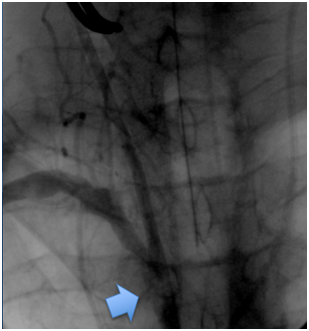

Cranioencephalic computerized tomography excluded acute ischemic lesions.CDS revealed severe stenosis of the innominate artery (PS 38 cm/s) (Figure 1), occlusion of right vertebral artery, total flow inversion of the right internal carotid artery (ICA) (Figure 2), partial endosystolic flow inversion of right CCA (Figure 3) and low amplitude anterograde flow of right external carotid artery, no significant lesions were found on the left carotid axis. Computerized tomography angiography (CTA) excluded significant carotid lesions and revealed pre-occlusive stenosis of the innominate artery by a calcic lesion (Figure 4).Surgical approach consisted of ultrasound-guided puncture of right brachial artery and surgical exposure of right CCA. Brain protection was achieved by direct clamping of the common carotid artery and subsequently carotid and axillary retrograde endovascular access was obtained. Placement of 6F introducer on brachial artery and 8F on right CCA (Figure 5). After pre-dilatation with a 4x40mm balloon (Admiral Xtreme™, Medtronic), a kissing stent technique was performed with a 6x59mm covered stent (AdvantaV12™, Getinge) on the right CCA and 7x57mm balloon-expandable stent (Visi-Pro™, Medtronic) on the right subclavian artery. At the end of the procedure direct expulsion of eventual embolic material was performed prior to declamping and a good permeability of the revascularized arteries was verified (Figure 6). Clamping time was under 1minute. The postoperative period was uneventful and patient was discharged 3days later.

Figure 5 Initial angiography. Blue arrow points the lesion.